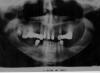

Ольга А. Опубликовано 18 сентября, 2007 Автор Поделиться Опубликовано 18 сентября, 2007 Грешно смеяться над больными! Посылаю снимок, на нем зубов немножко больше, чем я писала, но 1 слева и 2 и 8 справа доктор считает нежизнеспособными, а потому - удалить! 6 слева тоже под вопросом... Что скажете, уважаемые? "Полный съемный" не хочу!!! Ссылка на комментарий

Штаматолог Опубликовано 18 сентября, 2007 Поделиться Опубликовано 18 сентября, 2007 Грешно смеяться над больными! Посылаю снимок, на нем зубов немножко больше, чем я писала, но 1 слева и 2 и 8 справа доктор считает нежизнеспособными, а потому - удалить! 6 слева тоже под вопросом... Что скажете, уважаемые? "Полный съемный" не хочу!!! Снимок конечно не очень. Я правильно понимаю, что имплантацию Вы не рассматриваете? По хорошему там вообще я вижу только пару зубов, которые можно было бы сохранить. В любом случае подкову (несъемный протез) тут делать - деньги на ветер. А с нижней челюстью что будете делать, уже решили? Ссылка на комментарий

Doc Опубликовано 18 сентября, 2007 Поделиться Опубликовано 18 сентября, 2007 Снимок конечно не очень. Я правильно понимаю, что имплантацию Вы не рассматриваете? По хорошему там вообще я вижу только пару зубов, которые можно было бы сохранить. В любом случае подкову (несъемный протез) тут делать - деньги на ветер. А с нижней челюстью что будете делать, уже решили? Согласен. Подкова только в одном варианте: все убрать и на восьми имплантатах делать. Если на имплантацию нет денег, либо нет подходящего специалиста, то съемный на шариках, либо на какой другой конструкции. В принципе и полный съемный будет неплохо держаться безо всяких шариков. Но это уже самый дешевый и простой вариант. Ссылка на комментарий